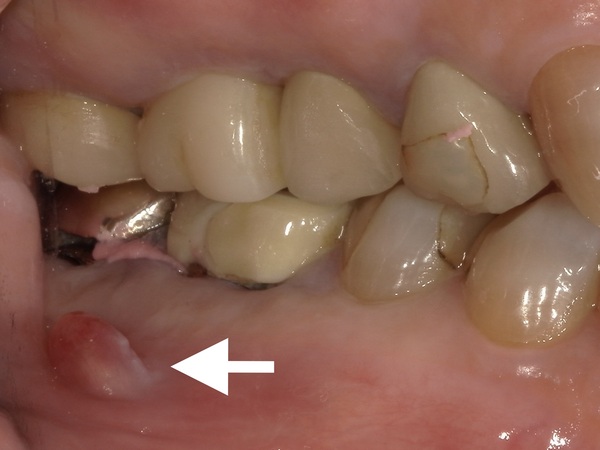

右下の6番目と7番目の歯には歯茎にフィステルという出来物がありました。

フィステルは右下6番目と7番目の根管治療(根の治療)の不備によって生じた膿の出口になります。

また、被せ物と歯茎の隙間に大きな虫歯があることも分かるかと思います。こちらの矢印が虫歯です。